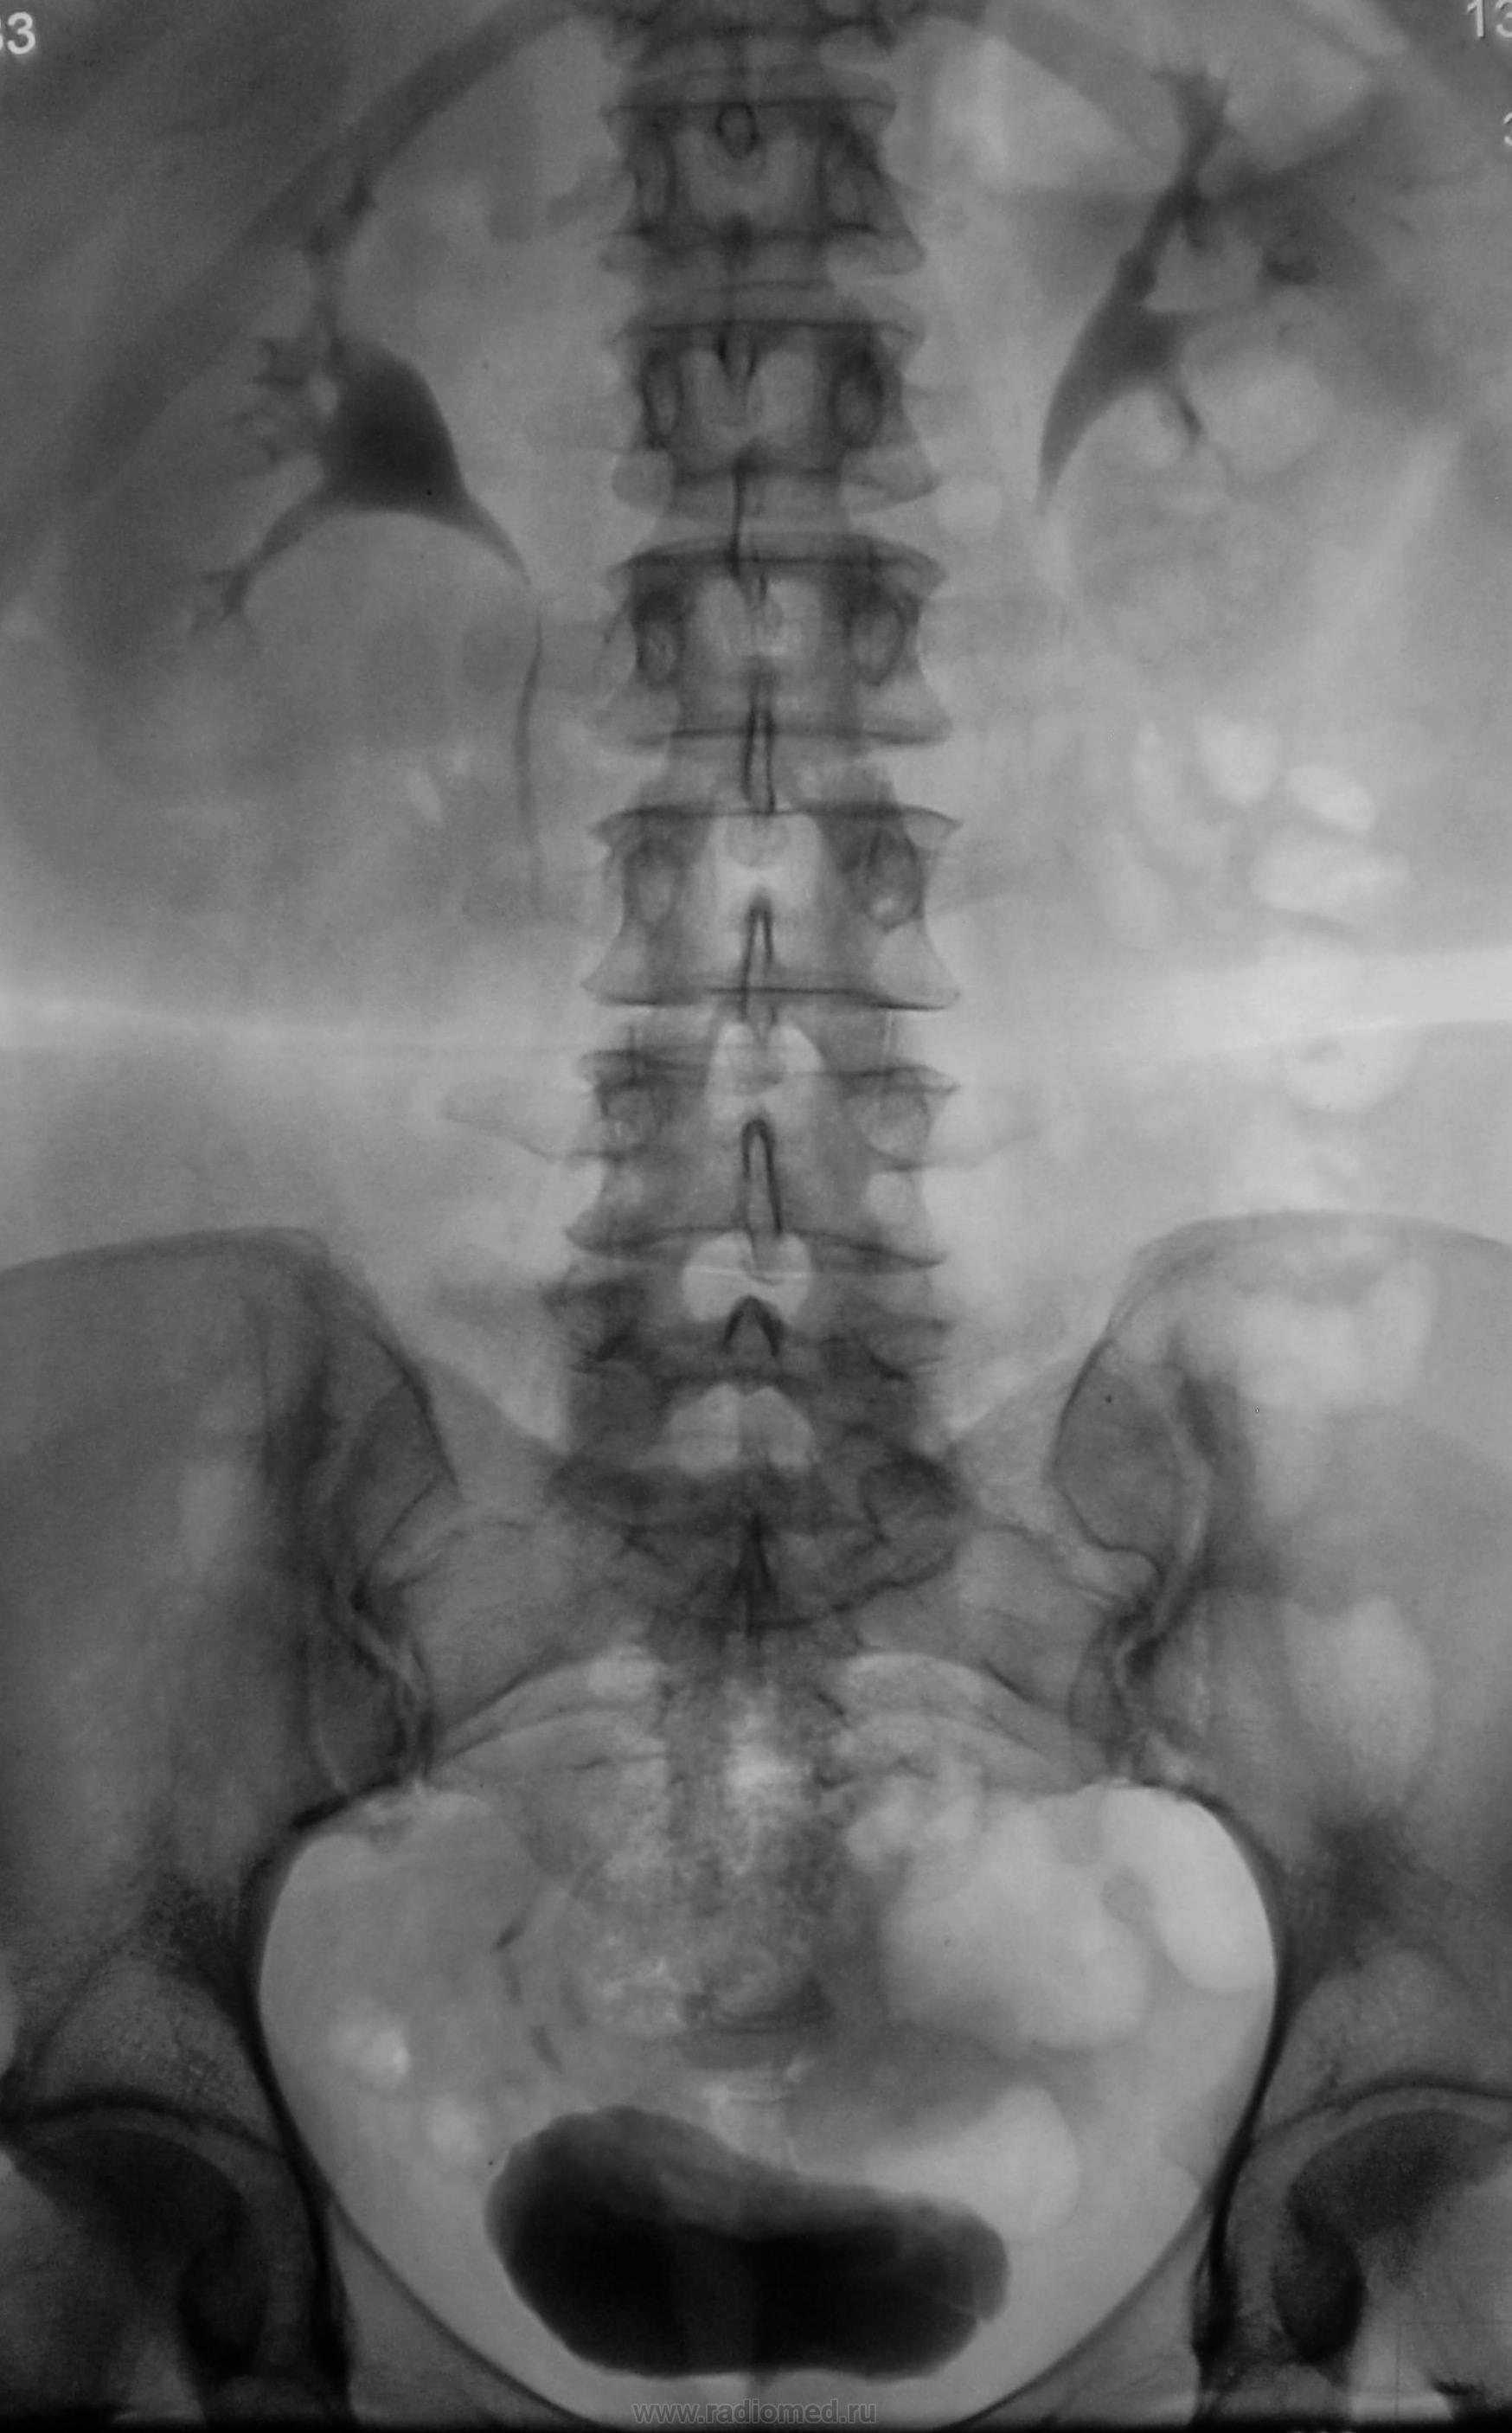

Сделали урографию, что писать протокольно просто не представляю… Может коллеги дадут совет?

Пациентка жалуется на боли, на уровне паховой области слева. В анализах все в норме.

левый мочеточник не законтрастирован. это настораживает. может быть всеже камень в левом мочеточнике?

1. Камень левого мочеточника, вблизи устья, и на обзорной он виден, без существенного нарушения оттока.

2. Крупная парапельвикальная киста правой почки.

3. Мочевой туго не выполнен (контрольное УЗИ!), но пациентке не помешает и УЗИ гениталий для уточнения состояния матки, особенно с учетом единичного обызествления в ее структуре.

Ну, пожалуй, киста; ну, допустим, обызвествление в матке…, но камень-то где ж?

Для устья низковато , пожалуй. И ЧЛС слева  вполне приличная , если- бы отток был нарушен левые форниксы такими-бы не были.      .. А за парапельвикальную кисту - мерси , не заметно сразу.

Полая система левой почки с увеличением.

Считаю, что Виктор Григорьевич прав с камнем левого мочеточника. Дилятация полостной системы почек НЕ всегда возникает при наличии камня мочеточника. Только при нарушении оттока (закупорка трубы). Вода всегда найдет себе путь! Различное НОРМАЛЬНОЕ положение матки (отклонение вправо, влево, антефлексио, антеверзио и.т.д) может давать различные варианты рентгенологических картин мочевого пузыря. Для дифдиагностики болей надо выполнить УЗИ малого таза (гинекология). Причин для тазовых болей у женщин более чем достаточно (миомы, кисты, варикозная болезнь и т.д.).